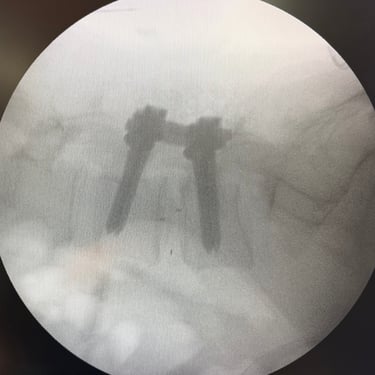

Síndrome Postdiscectomía: Tratamiento con Cirugía TLIF Mínimamente Invasiva

El síndrome postdiscectomía se presenta cuando persiste o reaparece el dolor lumbar y radicular después de una cirugía previa de hernia discal. Puede estar asociado a inestabilidad segmentaria, fibrosis epidural o degeneración discal progresiva. Cuando el manejo conservador no logra aliviar los síntomas, la fusión intersomática transforaminal (TLIF) mínimamente invasiva constituye una alternativa eficaz. Este procedimiento permite descomprimir las estructuras nerviosas, restaurar la altura discal y estabilizar el segmento afectado con menor daño muscular. La técnica mínimamente invasiva favorece menor sangrado, recuperación más rápida y mejores resultados funcionales.